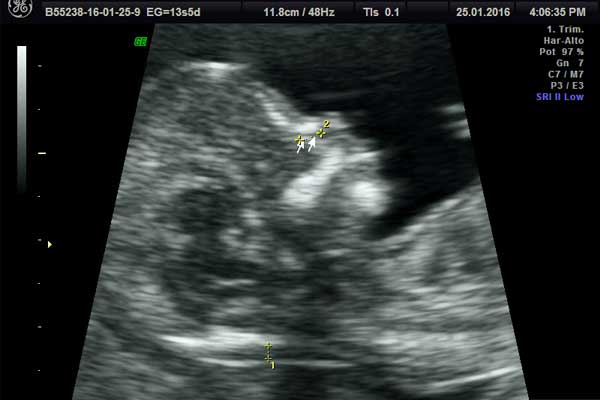

Translucencia nucal

El tamizaje genético es una prueba de detección precoz que ayuda a establecer si el bebé viene con problemas de tipo cromosómico.